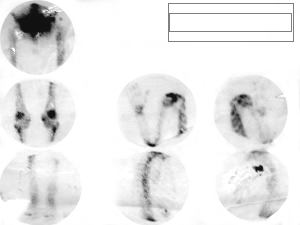

• Gammagrama óseo con captación normal.

Ganmagrama oseo - craneo - cuello - torax - abdomen- pelvis

Ganmagrama oseo - miembros